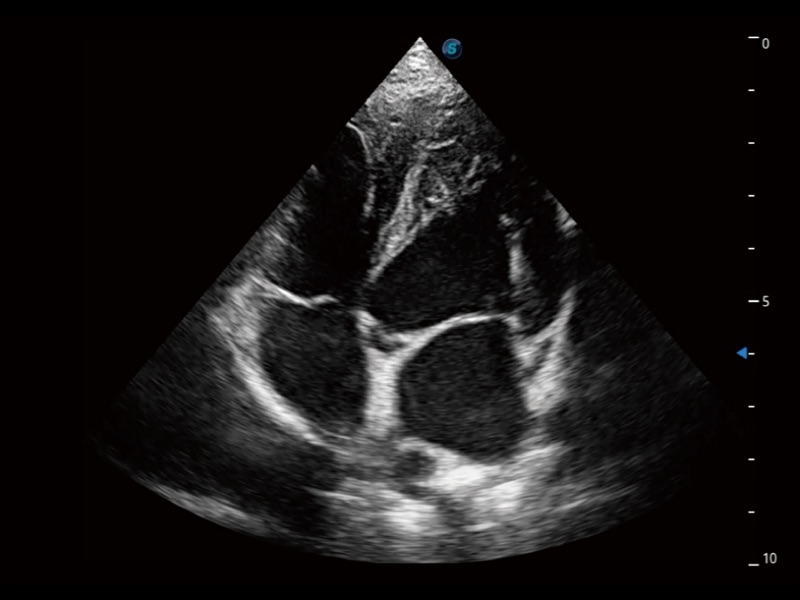

能夠基于左心室壁追蹤和辛普森法,自動計(jì)算射血分?jǐn)?shù),支持多個可移動點(diǎn)描跡,與手動測量相比,極大節(jié)省了動物醫(yī)生的時(shí)間和精力。

ProPet 70專為動物醫(yī)生設(shè)計(jì),對不同的動物體型和生理結(jié)構(gòu)作出了針對性的優(yōu)化。通過動物影像專用軟件,可滿足個性化的應(yīng)用需求,幫助動物醫(yī)生獲得更精確的診斷數(shù)據(jù)。

為精細(xì)結(jié)構(gòu)及組織邊緣提供高清晰度的圖像和更大的成像視野。幫助減輕醫(yī)生的用眼疲勞,快速精準(zhǔn)獲得測量的數(shù)據(jù)。